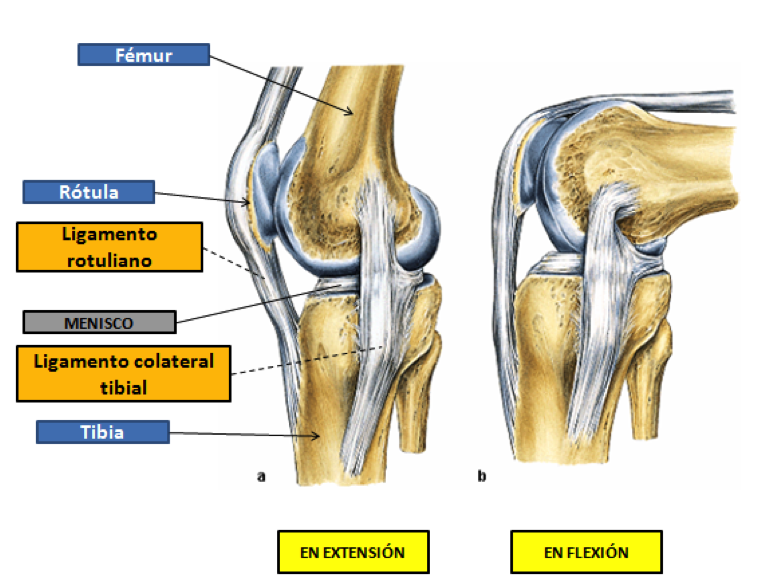

La articulación de la rodilla está asegurada por muchas estructuras ligamentosas (ligamento: tejido conjuntivo que une los huesos entre sí). La función de estos ligamentos es impedir que los huesos que forman la articulación se rocen entre sí con fuerza durante los movimientos y mantienen la estructura. En una visión exterior de la rodilla se pueden observar 3 ligamentos principales: ligamento rotuliano, ligamento colateral peroneo y ligamento colateral tibial.

La articulación de la rodilla está rellena por un líquido llamado líquido sinovial (fluido claro y viscoso, similar a la clara de huevo), este líquido no vamos a poder observarlo durante la disección, pues la cápsula que lo contiene estará rota en todas las muestras de rodilla que traigáis. La función de este líquido es reducir la fricción entre las superficies en contacto durante los movimientos de la pierna, lubricarla y acolcharla, además de nutrir y formar parte del sistema inmunitario de la articulación. Otros elementos que forman parte de la rodilla interna y que cumplen la función de evitar fricción entre los huesos, estabilizar y absorber el impacto de los choques de los movimientos de la rodilla son los meniscos. Los meniscos son dos anillos de tejido conectivo con forma de media luna que hay entre el fémur y la tibia.

Las patologías más frecuentes de la articulación de la rodilla son las lesiones en los meniscos y en los ligamentos. A los que os gusta el deporte, y concretamente el fútbol, puede que os suene la rotura del ligamento cruzado anterior, es una de las más frecuentes y complicadas que requiere cirugía en la mayoría de los casos. Se produce durante la actividad deportiva por giros enérgicos de la rodilla en los que el pie permanece en fuerte contacto con el suelo. En clase os enseñaré algún video sobre esto. RESUMEN DE OBJETIVOS DE LA DISECCIÓN - Localizar los huesos que forman la articulación: fémur, rótula y tibia. - Localizar los ligamentos externos de la rodilla: ligamentos colaterales y ligamento rotuliano. - Localizar los ligamentos internos de la rodilla: ligamento cruzado anterior y posterior. - Localizar y extraer los dos meniscos.